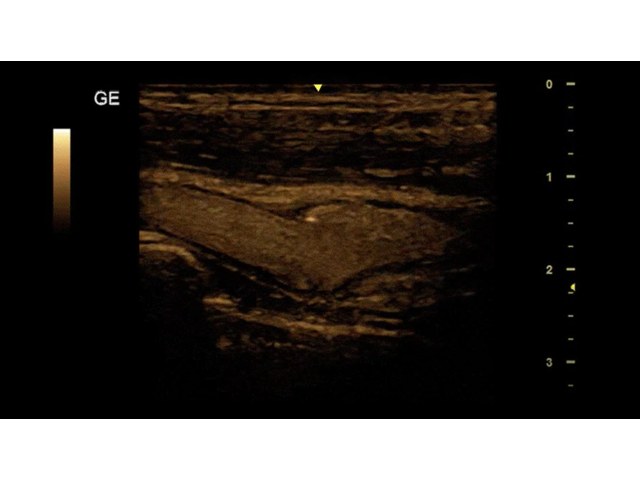

УЗИ-аппарат

GE Versana Essential

Ультразвуковой сканер GE Versana Essential отличается высокой точностью и мобильностью. Он широко используется при обследовании скелетно-мышечной системы и является незаменимым инструментом в урологии, гинекологии, педиатрии и общей радиологии.

Благодаря передовым технологиям и инновационным функциям, ультразвуковой сканер GE Versana Essential обеспечивает высокую четкость и детализацию получаемых изображений. Он позволяет врачам проводить диагностику и оценку состояния тканей и органов с высокой точностью, что способствует более точным и эффективным клиническим решениям.

Ультразвуковой сканер GE Versana Essential оснащен рядом инновационных технологий, которые расширяют его функциональность и улучшают процесс диагностики: